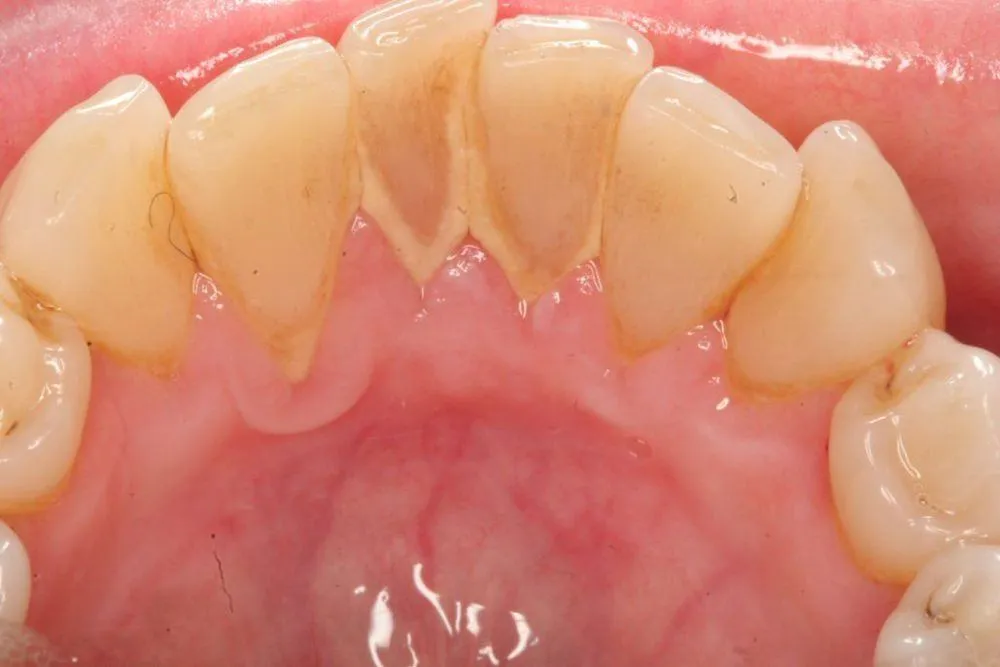

Cao răng là một vấn đề phổ biến mà nhiều người gặp phải. Không chỉ gây khó chịu, cao răng còn ảnh hưởng đến sức khỏe răng